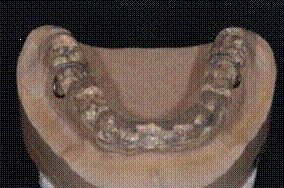

Изготавливаются шины лабораторным

способом с предварительным снятием слепков и определением центрального

соотношения челюстей.